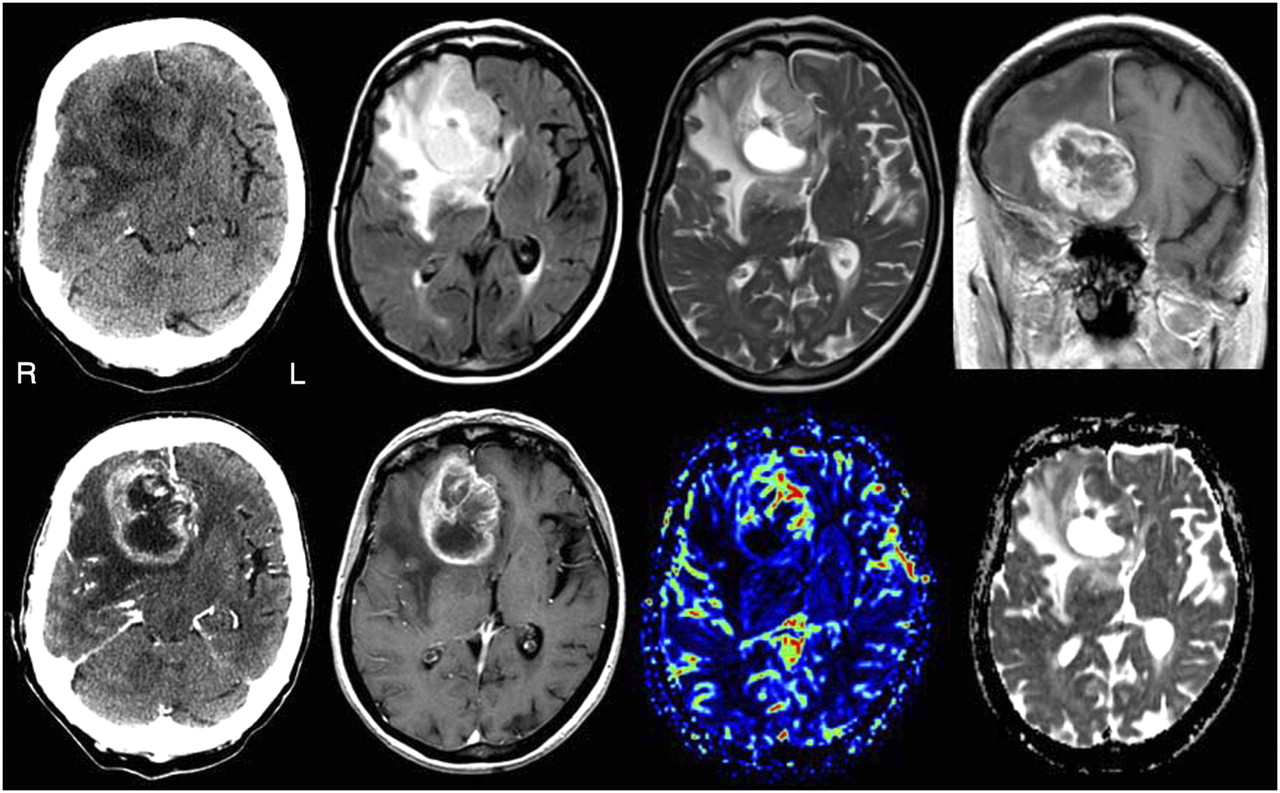

Использование новейших технологий визуализации позволило врачам увидеть мозг детально, что в свою очередь, помогло повысить точность, эффективность и безопасность операций.